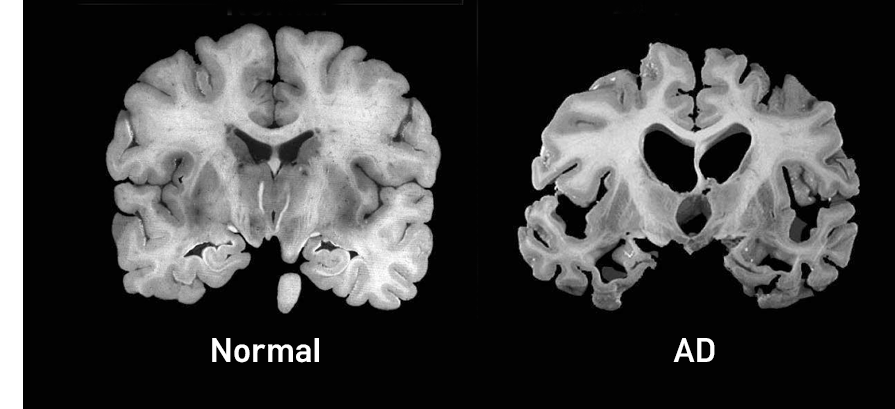

¾ËÃ÷ÇÏÀ̸Ӻ´Àº Ä¡¸Å¸¦ ÀÏÀ¸Å°´Â °¡Àå ÈçÇÑ ÅðÇ༺ ³úÁúȯ ¾ËÃ÷ÇÏÀ̸Ӻ´Àº ¸Å¿ì ¼¼È÷ ¹ßº´ÇÏ¿© Á¡ÁøÀûÀ¸·Î ÁøÇàµÇ´Â °æ°ú°¡ Ư¡. ¾ËÃ÷ÇÏÀ̸Ӻ´ÀÇ È£¹ß ¿¬·ÉÀº 65¼¼ ÀÌÈÄÀ̳ª µå¹°Áö¸¸ 40, 50´ë¿¡¼µµ ¹ß»ý |

Á¤È®ÇÑ ¹ßº´ ±âÀü°ú ¿øÀÎ ºÒ¸íÈ® ÇöÀç º£Å¸ ¾Æ¹Ð·ÎÀ̵å(beta-amyloid)¶ó´Â ÀÛÀº ´Ü¹éÁúÀÌ °úµµÇÏ°Ô ¸¸µé¾îÁ® ³ú¿¡ Ä§ÂøµÇ¸é¼ ³ú ¼¼Æ÷¿¡ À¯ÇØÇÑ ¿µÇâÀ» ÁÖ´Â °ÍÀÌ ¹ßº´ ÀÇ ÇÙ½É ±âÀüÀ¸·Î ¾Ë·ÁÁ® ÀÖÀ½ À¯ÀüÀûÀÎ ¿äÀÎÀÌ ¾à 40~50%¸¦ ¼³¸íÇÏ´Â °ÍÀ¸·Î º¸°í °¡Á··Â ȤÀº À¯ÀüÀû ¿äÀÎ ÀÌ¿Ü °í·ÉÀº ¾ËÃ÷ÇÏÀ̸Ӻ´ÀÇ ¹ßº´ À§ÇèÀ» Áõ°¡½ÃŰ´Â ÁÖ¿ä ¿äÀÎ |

¾ËÃ÷ÇÏÀ̸Ӻ´Àº ÀϹÝÀûÀ¸·Î 8~10³â¿¡ °ÉÃÄ ¼¼È÷ ÁøÇà ¸»±â Ä¡¸ÅÀÇ °æ¿ì ½Å°æÇÐÀû Áõ»ó°ú ±âŸ ½ÅüÀû ÇÕº´ÁõÀÌ µÇ¾î µ¶¸³ÀûÀÎ »ýȰÀÌ ºÒ°¡´ÉÇÏ¸ç ´ë¼Òº¯ ½Ç±Ý, ¿åâ, Æó·Å, ¿ä·Î °¨¿° µîÀÇ ÇÕº´ÁõÀ¸·Î »ç¸Á¿¡ À̸£°Ô µÈ´Ù. |